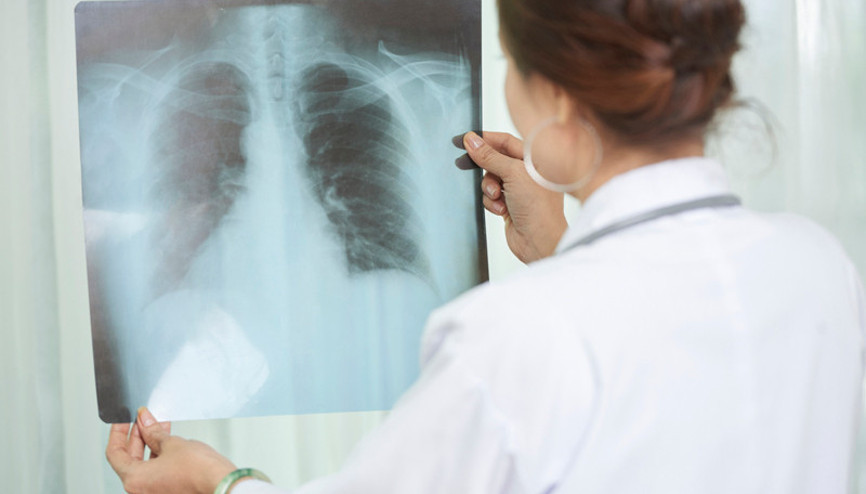

#Tüberküloz BelirtileriYüzyılın salgın hastalığı Covid-19’un ardından çok sayıda insanı etkileyen ve ölümüne neden olan ikinci önemli bulaşıcı hastalığın tüberküloz olduğunu biliyor muydunuz? Halk arasında ‘verem’ olarak da adlandırılan tüberküloz hastalığı dünyada her yıl milyonlarca kişinin kapısını çalıyor. Covid-19 pandemisinin tüberkülozun tanı ve tedavisini son derece olumsuz etkilediğini belirten Göğüs Hastalıkları Uzmanı Doç. Dr. Tülin Sevim, tüberkülozun en sık görülen 6 önemli belirtisini anlattı, önemli uyarılar ve önerilerde bulundu.

#VeremVeremli her 10 kişiden 3’ünün tanı konulmadığı için tedavi alamadığını belirten Doç. Dr. Hatice Eryiğit Ünaldı, “Dünyada her yıl 10 milyon yeni veremli hasta ortaya çıkmaktadır. Yetersiz beslenme, sigara kullanımı, diyabet, HIV enfeksiyonu, verem için risk faktörleridir. 2019 yılında her 22 saniyede bir kişi verem nedeniyle hayatını kaybetmiştir” dedi, bu hastalık hakkında önemli bilgiler verdi.

#TanyeliDünya Sağlık Örgütü (DSÖ) yetkilileri, geçen yıl 8,2 milyon vakayla rekor kıran tüberkülozun artık 'en önde gelen bulaşıcı hastalık’ olduğu uyarısında bulundu. Viktorya döneminde verem olarak bilinen hastalığın erken evrelerinin soğuk algınlığı ya da gribe benzediği, ancak bulaştığı her altı kişiden birini öldürebileceği konusunda yetkililer uyarıyor.

#MeyveDünya Sağlık Örgütü (DSÖ) yetkilileri, geçen yıl 8,2 milyon vakayla rekor kıran tüberkülozun artık 'en önde gelen bulaşıcı hastalık’ olduğu uyarısında bulundu. Viktorya döneminde verem olarak bilinen hastalığın erken evrelerinin soğuk algınlığı ya da gribe benzediği, ancak bulaştığı her altı kişiden birini öldürebileceği konusunda yetkililer uyarıyor.